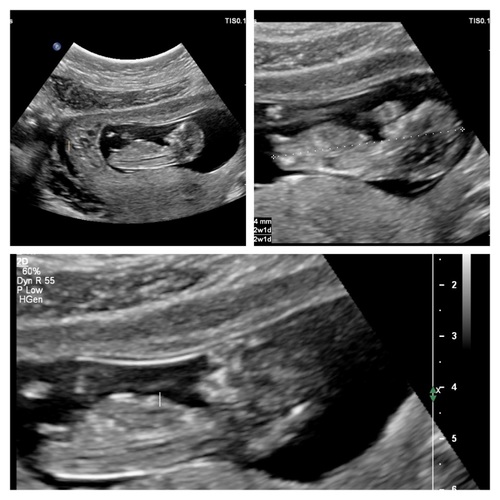

Wat denken jullie meisje of een jongetje.. spannend!

Jongen denk ik, ook de nub馃挋

Wat denk je van mijne ?

Nouja volgens nub test is de kans groot dat jij een meisje krijgt xx